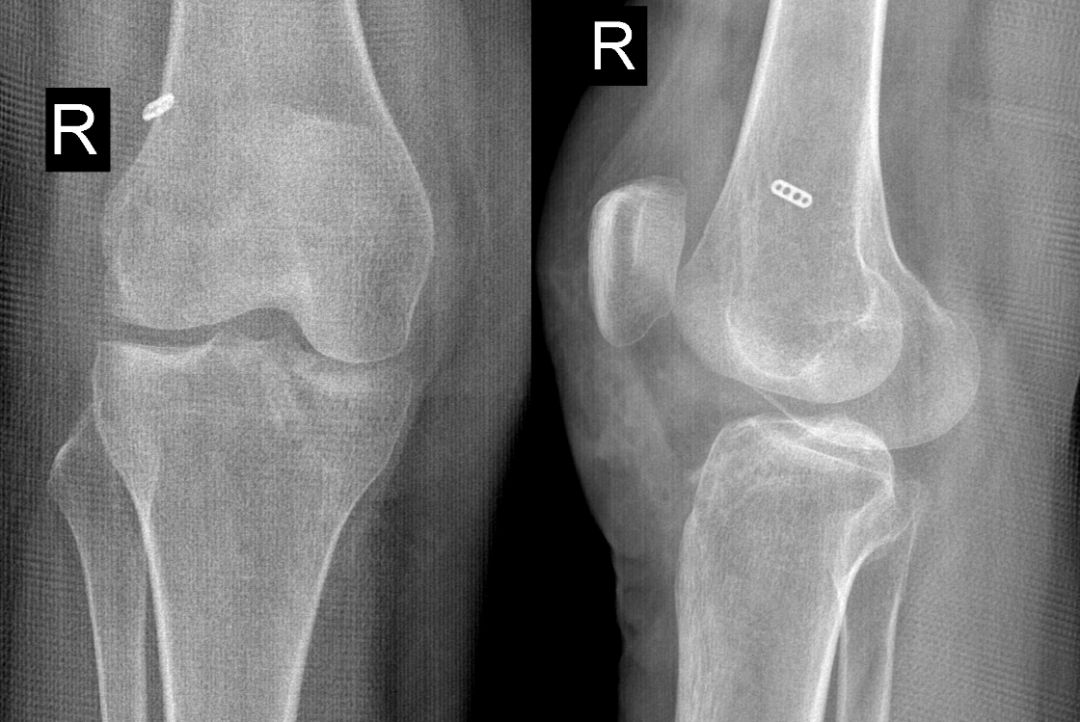

ACL损伤的间接征象:指ACL断裂后胫骨前移位出现的一系列改变。间接征象只能考虑可能有ACL损伤。

1.关节失稳,ACL撕裂,胫骨就相对于股骨前移。

有时前交叉韧带损伤或撕裂,须与半月板撕裂相鉴别,如下例

箭头是撕裂的内侧半月板,前交叉韧带冠状面是连续的,下端胫骨附着处小片绪状高信号影,提示损伤或部分撕裂。